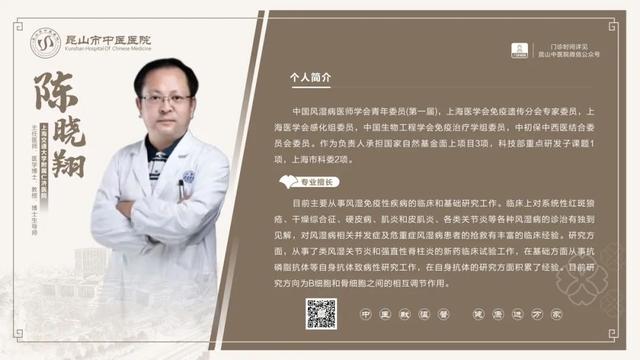

6��23��-6��29��������ר�ҳ���һ����

������鿴��ͼ���Ե���ʵ�ʳ���Ϊ��

6��23��-6��29�������dz���ר�ҽ���